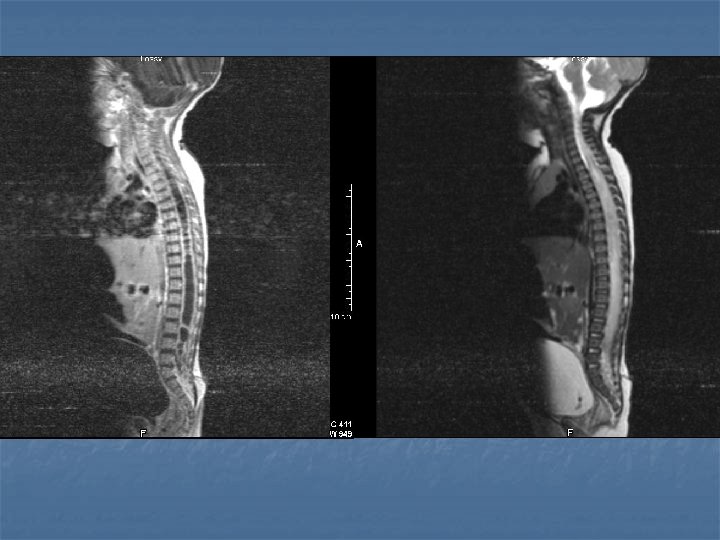

Epidural Ampiyem- 3 è Tanı è Direkt grafi è Pott gibi kronik infeksiyonlarda osteomyelite bağlı deformiteler görülür è Radyonükleid è Ga 67 scanning (met, dejeneratif hast. karışabilir) è CT è kemikdestüksiyonu è MR è T 1 è hipo , T 2 Hiper + yumuşak doku tutulumu Myleografi è Demode ve tehlikeli

Osteomyelit- 5 è Kronik dönemde deformite ortaya çıkar è Tanı è Direkt grafi è 3 -6 haftada ilk bulgular (endplate erozyonu, disk mesafesi daralması, korpus vertebrada rarefaksiyon, kifoz eğilimi) è Radyonükleid è Tc 99 scanning pirofosfat ile %80 spesifisite è CT è MR è Etkenler è Staph aureus, pseudomonas (İV madde bağımlıları) , Tbc